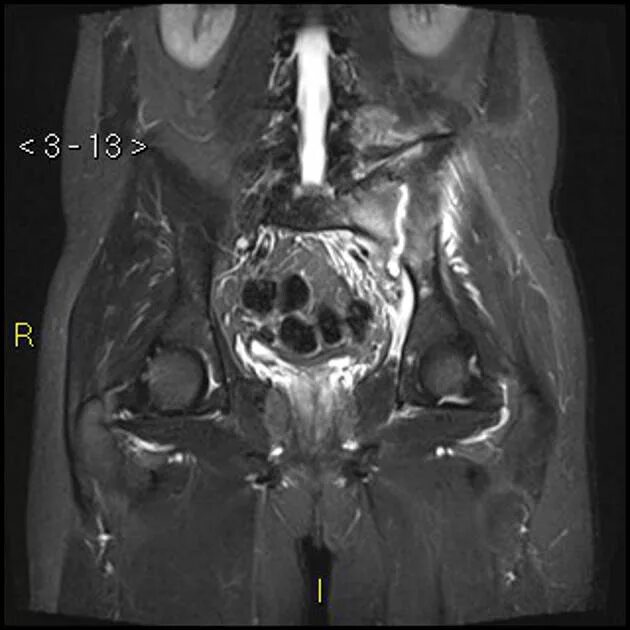

Мрт пояснично крестцового отдела тазобедренные суставы